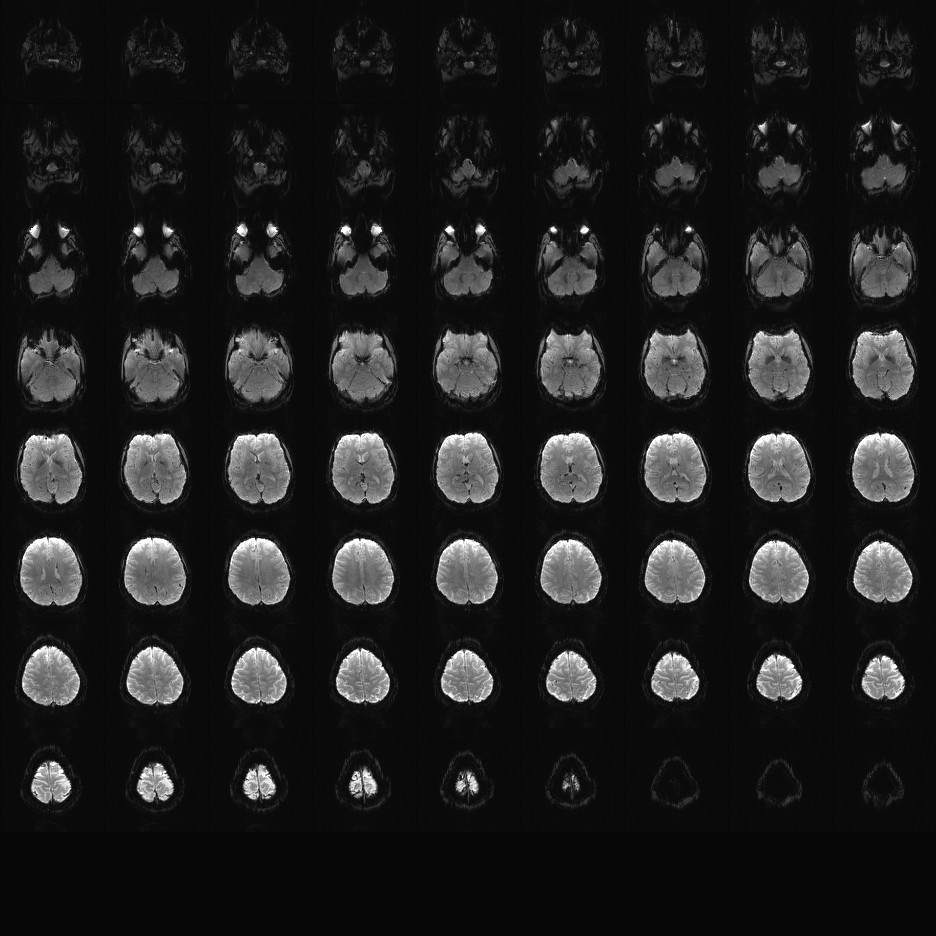

Multi-banded RF pulses can be used to accelerate volume coverage along the slice direction by simultaneously exciting and acquiring multiple slices and subsequently unaliasing them using parallel imaging principles and the spatial information available in multi-channel RF array coils.

This allows for a direct reduction in the volume TR by the number of simultaneously excited slices (i.e., the multiband (MB) factor or the slice acceleration factor).